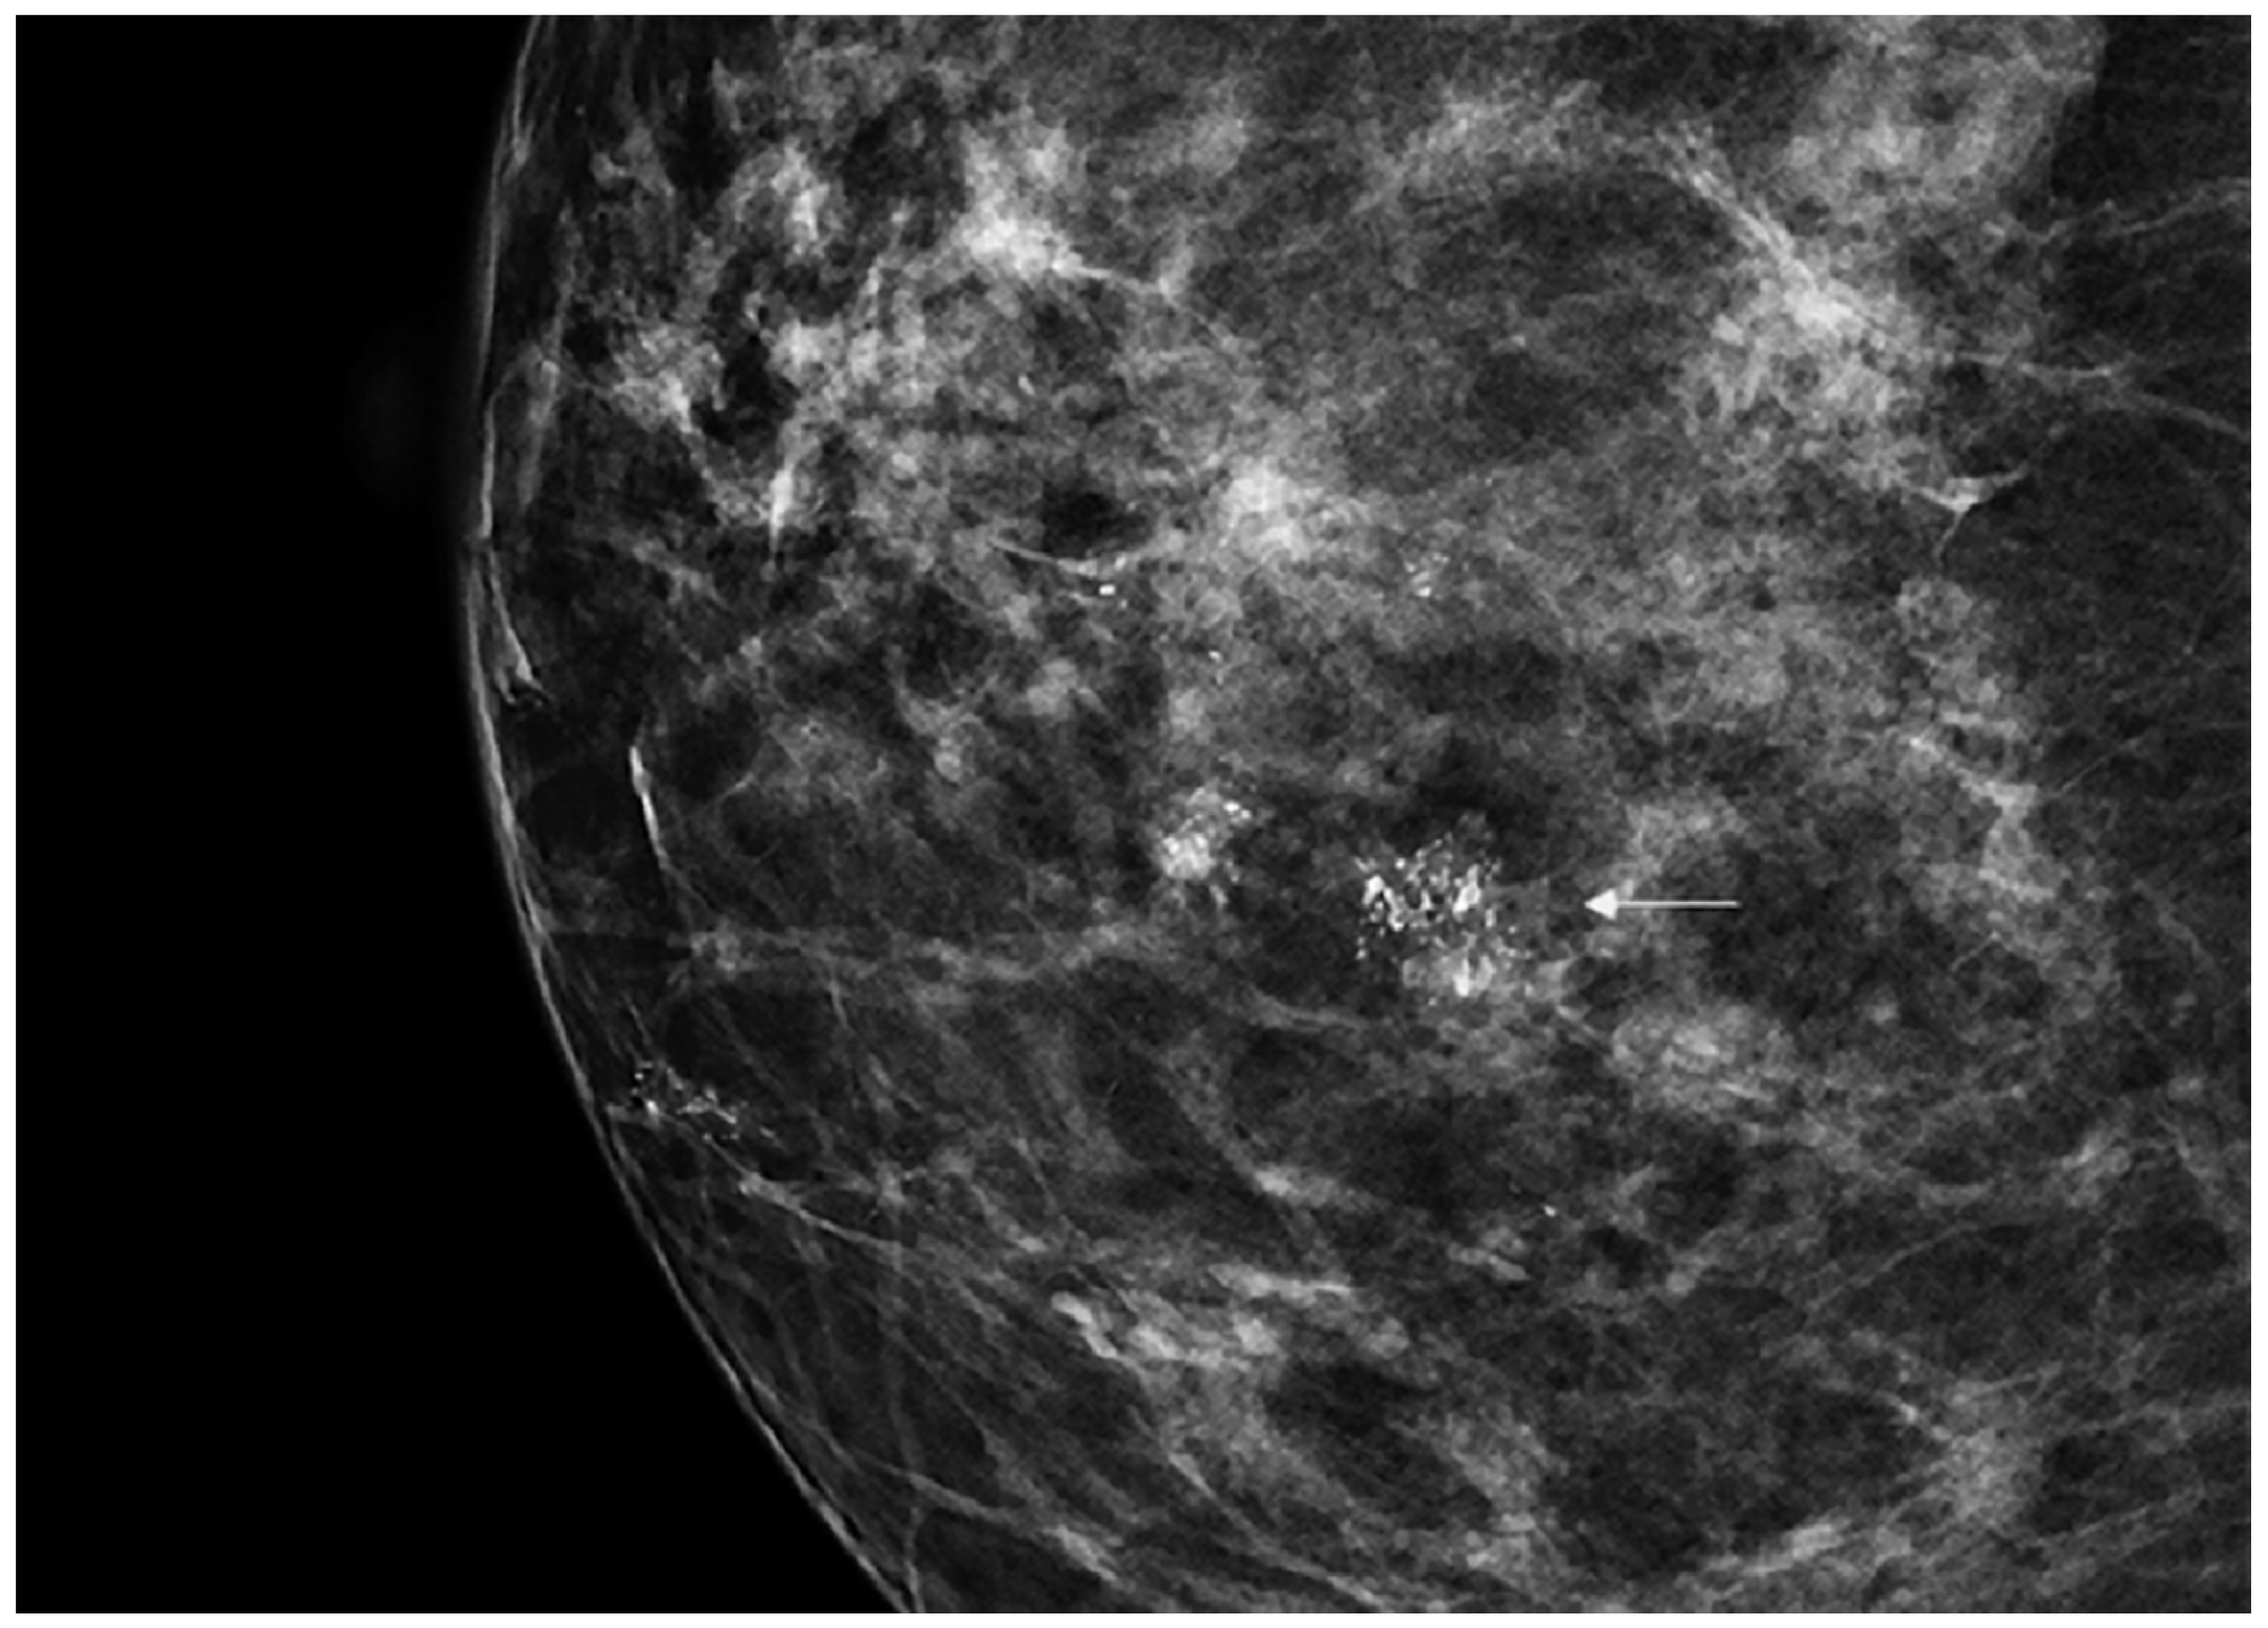

DCIS is usually diagnosed by imaging because it is often clinically occult. Its incidence has rapidly increased from 1980 considering the dramatic improvement in diagnosis and screening imaging tools. Mammography (Figure 1) plays a central role, since it is the cornerstone of breast cancer screening and diagnosis [2].

Figure 1. Spot magnification mammogram with a small cluster of pleomorphic microcalcification (arrow) suspicious for ductal carcinoma in situ (DCIS)/ductal intraepithelial neoplasia (DIN).